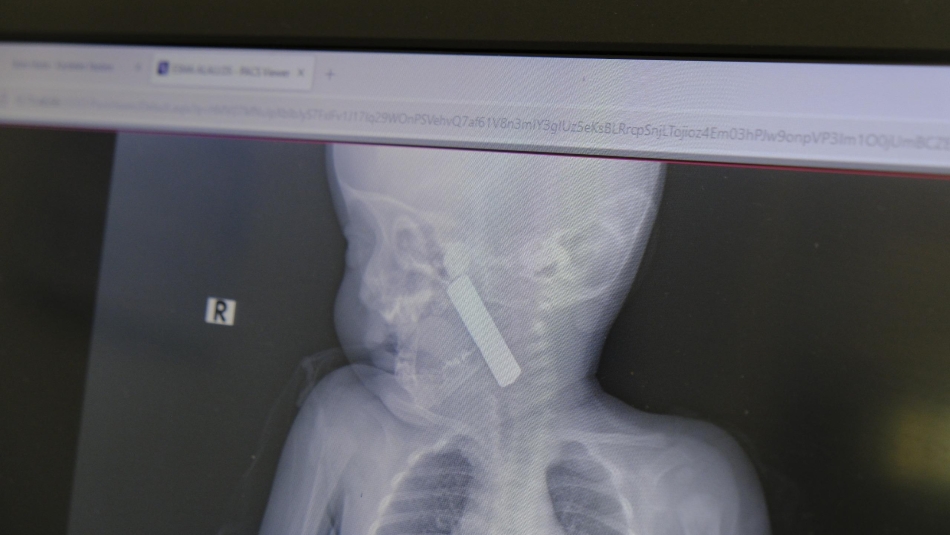

Edinilen bilgiye göre, kusma şikayeti ile ailesi tarafından Karaman Eğitim ve Araştırma Hastanesi acil servisine getirilen 6 aylık E.A. isimli kız bebeğin, yapılan muayene ve tetkiklerde boğazında kumanda pili kaçtığı tespit edildi. Solunum sıkıntısı da yaşayan bebek hemen ameliyata alındı. Çocuk Cerrahisi Uzmanı Doç. Dr. Mehmet Uysal tarafından yapılan ameliyatla bebeğin boğazındaki pil çıkarıldı.

Yaşanan olayla ilgili bilgi veren Doç. Dr. Mehmet Uysal, "Acil polikliniğimize kusma şikayeti ile 6 aylık bir kız bebek getirilmiş ve bize haber verildi. Biz de vakit kaybetmeden geldik, hastamızı gördük. Yapılan tetkikler sonucunda, ağız tabanına oturan ve yemek borusunun birinci darlığına kadar uzanan, kumanda pili dediğimiz bir pille karşılaştık. Filmde ve muayenede bunu gördük. Hastayı ilk gördüğümüzde bayağı siyanotik durumda, solunum sıkıntılıydı ve oksijen satürasyonu 90 civarındaydı. Böyle olunca bir an önce beklemeden hızlı bir şekilde ameliyathaneye götürdük. Orada ameliyathanedeki anestezi uzmanlarımız ve personel bize yardımcı oldu, hasta hızlı bir şekilde entübe edildi. Ondan sonra da laringoskop ve magill forseps dediğimiz malzemelerimizle bu yabancı cismi çıkarmış olduk. Bir an evvel müdahale ettik, iyi ki müdahale ettik, orada ağız tabanında, özellikle ön kısmında hasar oluşmuştu. Müdahale sonrasında da hastanın solunum problemleri bir süre devam etti, bu yüzden 24 saat takip ettik. Herhangi bir problem oluşmayınca 24 saat sonra kontrole gelmek üzere hastayı taburcu ettik" diye konuştu.